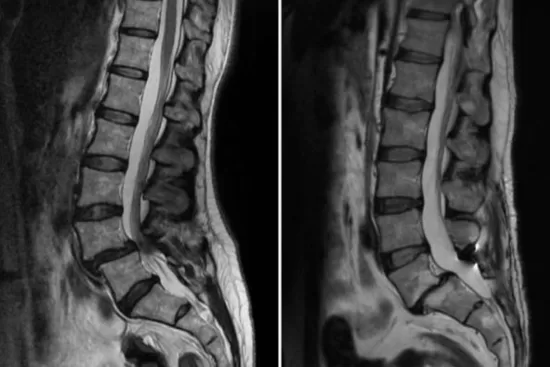

El diagnóstico de esta afección requiere varias pruebas. Las radiografías son útiles para obtener imágenes de la columna vertebral y localizar la vértebra afectada. La resonancia magnética (RM) es otra herramienta clave que ofrece imágenes detalladas de los tejidos blandos y estructuras vertebrales mediante un potente imán conectado a un ordenador. Por último, la tomografía computarizada (TC) sirve para crear imágenes tridimensionales de la columna, ayudando a visualizar el desplazamiento vertebral con mayor precisión.